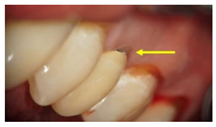

GroupDescription Clinical Presentation

Group-II (n = 30)Received a Co-Cr ceramic prosthesis fabricated by a computer-aided design and computer aided manufacturing (CAD/CAM) using Sintron technology. Copings were milled from a soft pre-sintered Co-Cr alloy by CAD/CAM, sintered in a special oven and followed by porcelain layering.Molecules 26 01331 i002

Arrows show the crown margins and gingival tissues interface.